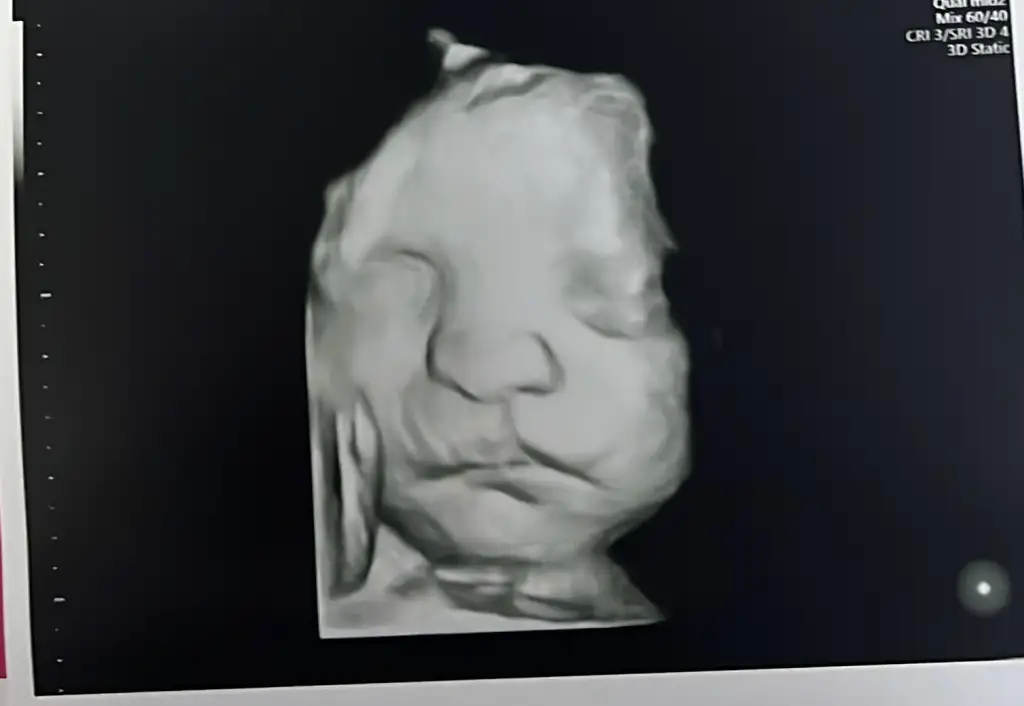

34+1 canım inşallah yüzünü gösterir senin kızçedeOy maşallah çok net çıkmış bende pazartesiyi iple çekiyorum doğru düzgün göstermedi bizim kız kendinibu arada kaç haftalıksın

Eki Görüntüle 3662548 Eki Görüntüle 3662549

Teyzoşlar bizim boyumuzda posumuzda günümüzle uyumluymuş

Hiçbir sıkıntı gözükmüyor dediya bakarmısınız şunun dudişine ısırcam yanaklarınıda yicemmm